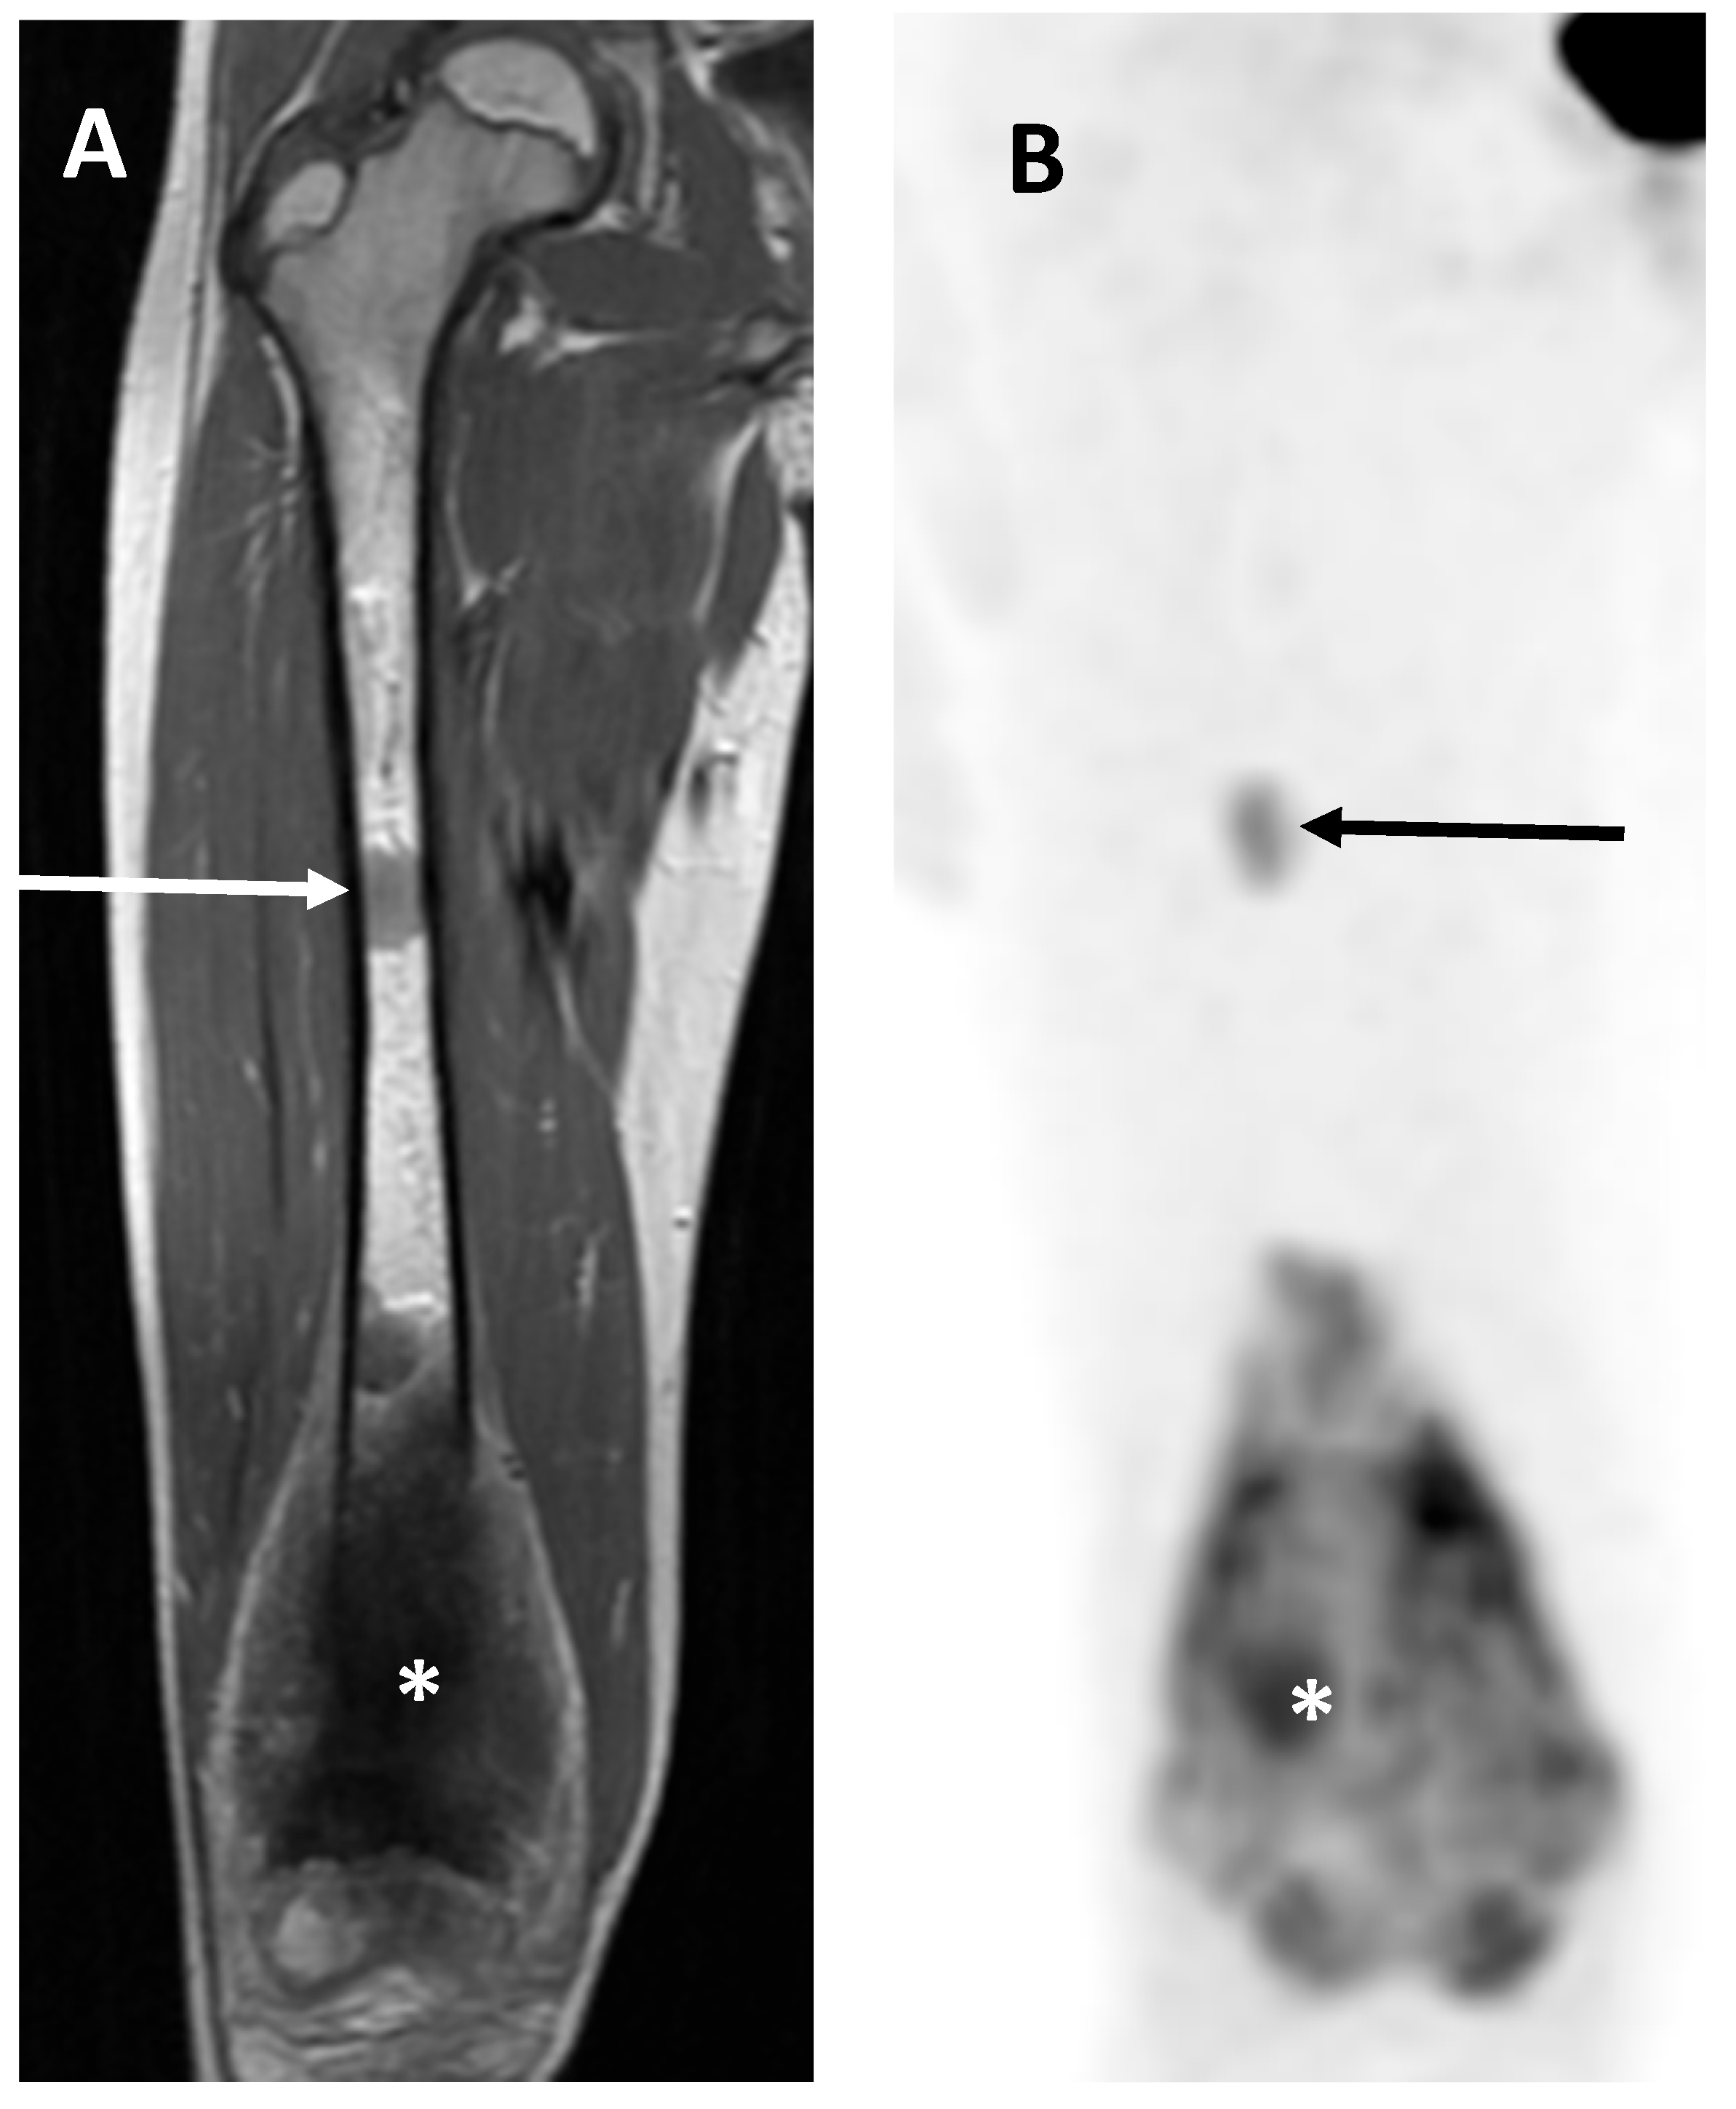

- Saifuddin, A.; Michelagnoli, M.; Pressney, I. Skip metastases in high-grade intramedullary appendicular osteosarcoma: An indicator of more aggressive disease? Skelet. Radiol. 2021, 50, 2415–2422. [Google Scholar] [CrossRef] [PubMed]

- Ahmed, A.R. Secondary bone lesions in the affected limb in osteosarcoma (skip lesions), its classification and prognosis. Arch. Orthop. Trauma Surg. 2011, 131, 1351–1355. [Google Scholar] [CrossRef] [PubMed]